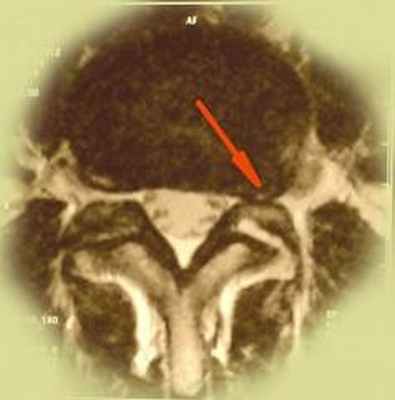

![]() | Фораминальная грыжа диска - редкий тип грыж диска, может сочетаться с истмическим спондилолизом, который в свою очередь дагностируется при спиральной компьютерной томографии. Сложен в диагностике, так как в просвете позвоночного канала грыжи не находят, но боли очень сильные. В этом случае небольшая - 3-4мм грыжа диска располагается в самом узком месте - фораминальном отверстии, где совсем небольшой кусочек хряща может сильно зажать нервный корешок. Лечение исключительно хирургическое. |

Под фораминальной грыжей позвоночника понимают выпячивание фиброзного кольца межпозвоночного диска за пределы его нормального анатомического расположения в фораминальное отверстие - место, где располагаются корешки спинномозговых нервов.

Этот вид грыжи считается наиболее опасным, так как в результате выхода фиброзного кольца происходит защемление нервных корешков. При этом пациент испытывает сильные болевые ощущения, нарушается двигательная активность, что значительно ухудшает качество жизни больного.

Чтобы понять что такое грыжа и как она образуется следует сначала рассмотреть как выглядит здоровый сегмент позвоночника с межпозвоночным диском. Межпозвоночный диск состоит из фиброзного кольца и пульпозного ядра желеобразной консистенции. В непосредственной близости с диском проходит спиной мозг в твердой мозговой оболочке. Отходящий от него спино-мозговой нерв с чувствительным и двигательным корешком лежит в костном ложе – фораминальном отверстии. В нормальных условиях в нем достаточно места для данного нервного образования. Фораминальная грыжа диска l4 l5 – это выпячивание фиброзного содержимого хряща за его нормальные пределы в фораминальное пространство. В результате такого выпячивания происходит ущемление спинномозгового нерва, что, безусловно, вызывает сильные болевые ощущения и становится причиной нарушения двигательной активности и работоспособности человека. Именно этот вид грыжи считается наиболее опасным.